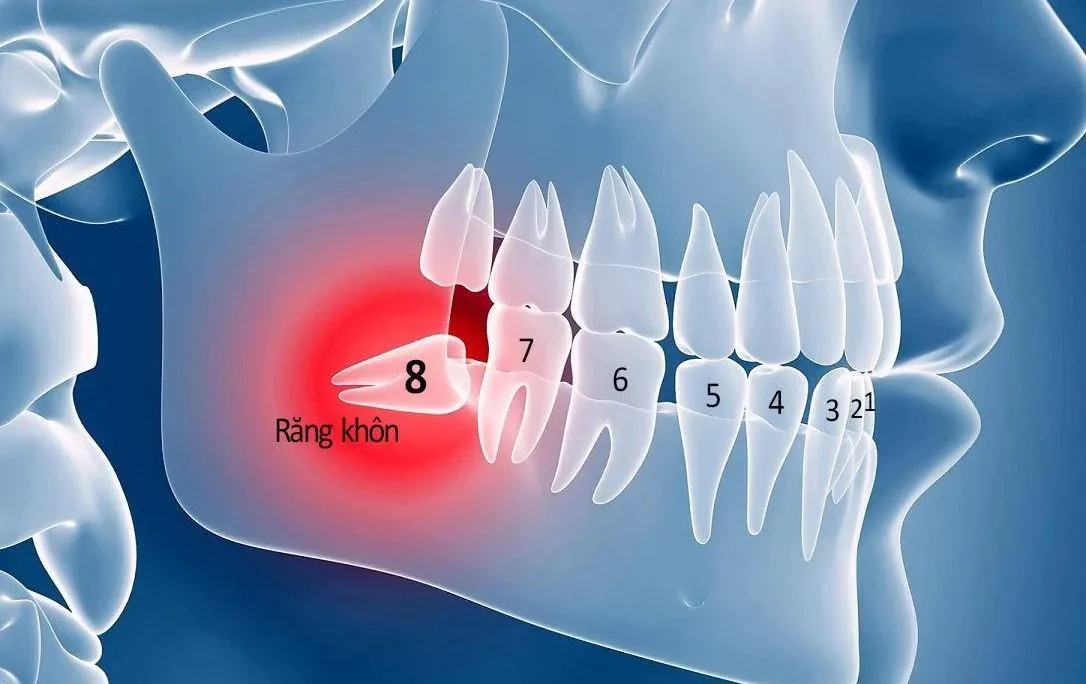

- Sâu kẽ răng hàm: Khi kẽ răng hàm bị sâu, do vị trí răng hàm nằm sâu bên trong nên rất khó để nhận biết ở giai đoạn đầu. Nhiều người chỉ phát hiện khi bệnh đã tiến triển nặng, lan rộng và ảnh hưởng đến các răng bên cạnh.